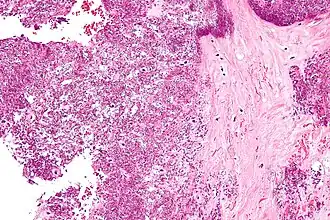

| Microfotografia mostrando a deposição de cristais em um disco intervertebral. Coloração H&E. | |

Cristais de Deposição De Pirofosfato De Cálcio Diidratado tendem a formar dentro de tecidos articulares. O diagnóstico é feito por microscópio, com a análise do fluido de uma junta. Radiografias da junta podem mostrar sinais de Condrocalcinose. Depósitos Assintomáticos podem se formar na cartilagem, articulações, discos intervertebrais, tendões e ligamentos. A deposição de cristais dentro da cartilagem (hialina e fibrocartilagem) é conhecido como condrocalcinose. É inicialmente só visível no microscópio, mas se houver bastante calcificação, pode ser visto com a ajuda da radiografia também. Locais comuns de condrocalcinose incluem os joelhos, punhos, cotovelos, e quadris.